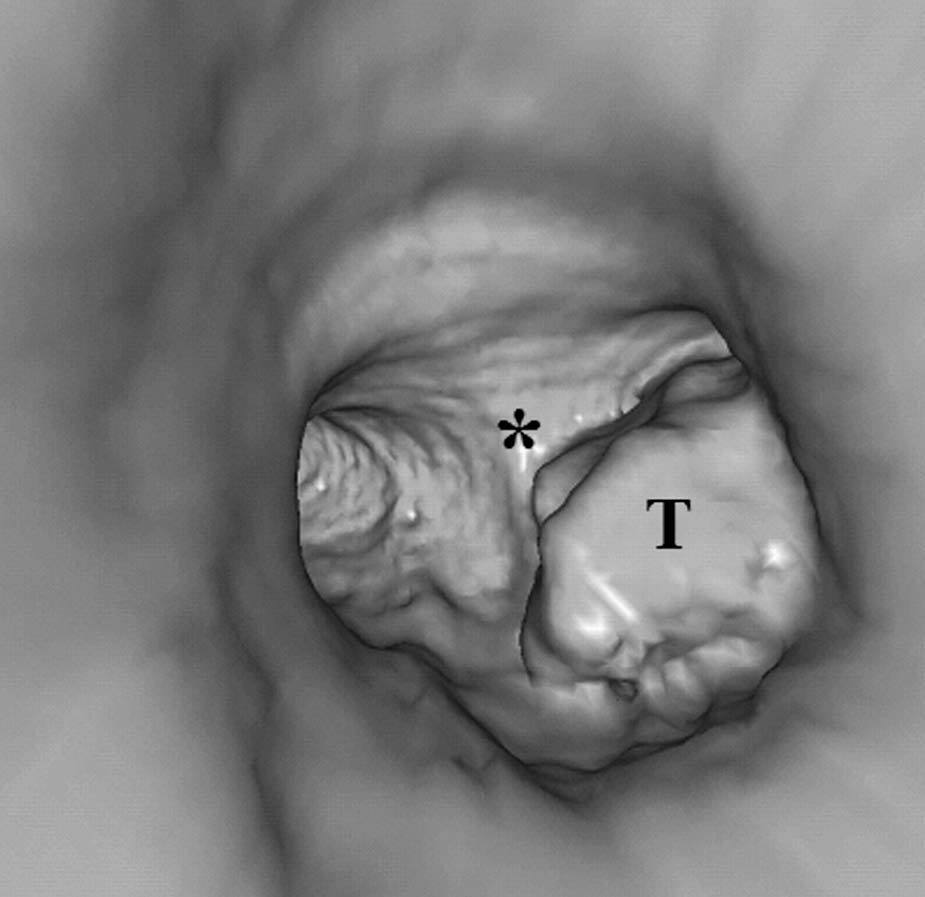

Pese a las conocidas limitaciones de la TC, ésta continúa siendo la técnica de elección en la estadificación del tumor en los pacientes con CPNM; su sensibilidad y especificidad en la determinación de la infiltración de pared oscilan entre el 38 y el 87% y del 40 al 90%, respectivamente, según las series. El desarrollo de nuevos equipos de TC helicoidal y principalmente las TC multidetectoras (TCMD) proporcionan unas imágenes 2D de mayor resolución con la posibilidad de hacer reconstrucciones multiplanares (MPR) en distintos planos del espacio e incluso 3D con la consiguiente mejora de la valoración del tumor, su extensión e infiltración de estructuras vecinas5 (fig. 4). Así, con la TCMD se puede poner de manifiesto con mayor fiabilidad la invasión de la cisura, la pared torácica o el mediastino, y además es capaz de determinar, gracias a las reconstrucciones de volumen, la relación exacta del tumor con la vía aérea (fig. 5). El progreso en la capacidad diagnóstica deriva del incremento en la resolución de las imágenes obtenidas y de la posibilidad de emplear nuevas aplicaciones como la broncoscopia virtual y la visualización en tiempo real. La broncoscopia virtual es útil para valorar la invasión del árbol traqueobronquial con la finalidad de planificar la cirugía, también como guía para el fibrobroncoscopista y, por último, porque permite ver el árbol bronquial distal a la estenosis (fig. 6)6. La capacidad de ver la imagen en tiempo real es especialmente útil cuando se emplea como guía en maniobras intervencionistas como biopsias percutáneas, ya sea con finalidad diagnóstica o como parte de la estadificación (fig. 7). Esta técnica de guía de biopsia denominada TC fluoroscopia reduce el número de pases y el tiempo global de la exploración, implica un menor riesgo de lesión de estructuras y permite la visualización inmediata de las posibles complicaciones7.

Fig. 6.--Broncoscopia virtual. (A) Reconstrucción coronal que muestra una masa hiliar derecha (T) con infiltración del ángulo traqueobronquial. (B) Visión endoscópica del tumor en la que se observa la infiltración de la tráquea y la relación con la carina (asterisco).